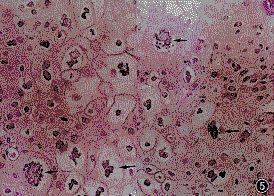

女性宫颈尖锐湿疣病检图

尖锐湿疣是由人类乳头瘤病毒(HPV)感染引起的一种性传播疾病。主要类型为HPV1、2、6、11、16、18、31、33及35型等, HPV16和18型长期感染可能与女性宫颈癌的发生有关。